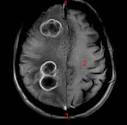

Exemples d'images d'abcès :

Lésion temporo pariétale droite arrondie, dont le centre apparaît en hypersignal de diffusion avec une restriction du coefficient apparent de diffusion et avec une coque en hypo-isosignal T2.

La lésion apparait en hyposignal T1, avec prise de contraste de la périphérie en cocarde, elle est entourée d'un œdème périlésionnel en doigt de gant.

En scanner, typiquement, l'abcès cérébral donne une image en cocarde cernée d'un halo d'oedème. La zone centrale hypodense représente le pus de l'abcès, elle est entourée par un anneau plus ou moins épais, régulier, iso- ou hypodense et prenant fortement le produit de contraste. Cet anneau est entouré d'un halo hypodense qui représente l'oedème péricérébral.

En IRM, elle montre une lésion hypo-intense en T1, hyperintense en T2 ; la lésion est soulignée en périphérie par une intense prise de contraste. On note sur les séquences en T2 une fine couronne périphérique, régulière, nettement hypo-intense, caractéristique des abcès cérébraux. La chute de l'ADC permet d'écarter une métastase ou une tumeur nécrotique.